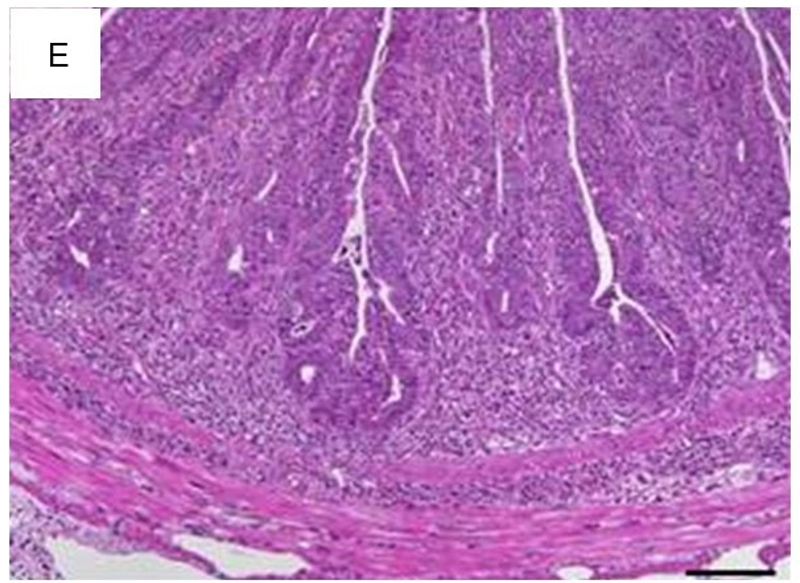

白细胞浸润固有层,这是所有肠炎模型的共有特征。尽管浸润了不同比例的嗜中性粒细胞、嗜酸性粒细胞、单核细胞、浆细胞和淋巴细胞,评估每高倍视野(HPF)组织内混合的炎症细胞,可充分反映了炎症相关的变化(图1A)。散在中性粒细胞是轻度浸润的典型特征(图1B)。从炎症细胞的主要局部粘膜定位开始(图1C),严重程度增加首先包括粘膜下层(图1D),随后延伸至固有肌层并最终导致透壁浸润(图1E)。最初见于上皮细胞层的主要变化包括隐窝上皮细胞增生,杯状细胞的损失,隐窝炎、隐窝脓肿和糜烂。

1(E)透壁炎症细胞(×200;比例尺50µm)